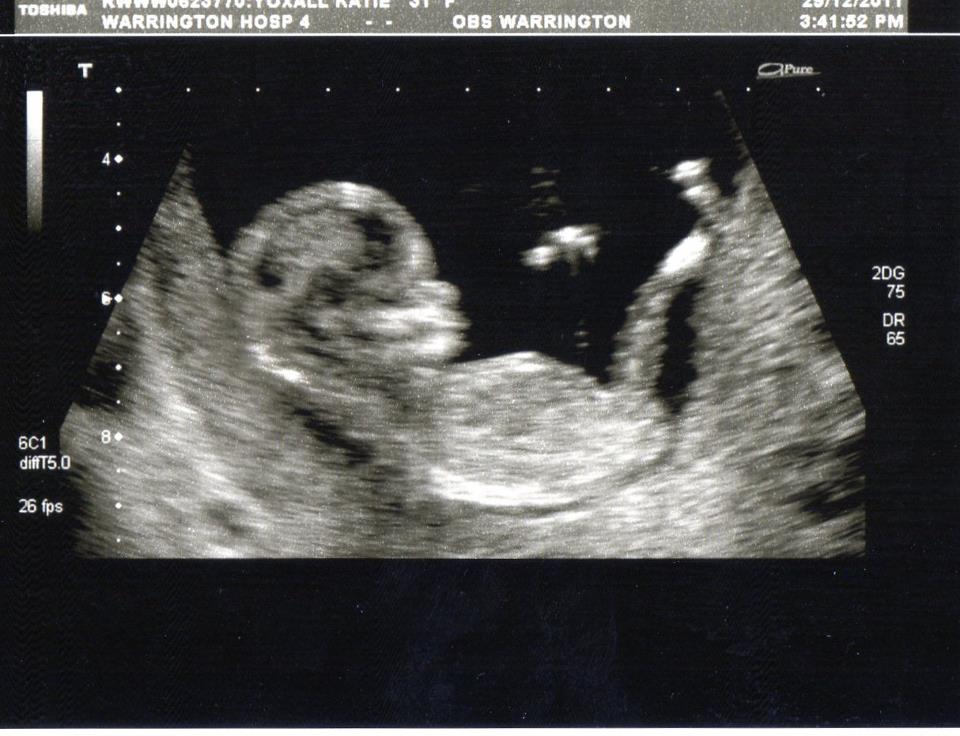

Hi everyone, my girlfriend and i are expecting a new little bundle of joy in July and we were wondering if anyone would like a guess at what we could be expecting? All guesses gratefully received and we will keep you updated when the 20 week gender scan arrives. Many thanks in advance!!

Attachment 1082